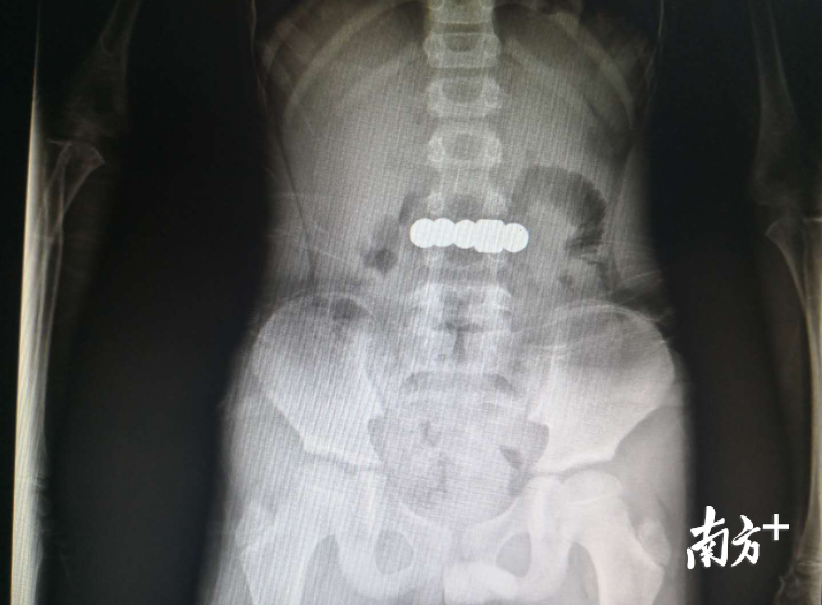

“非常危险”,周正说,X光显示,这些珠子直径达五六个毫米,四颗钢珠和磁铁紧紧地吸在一起,形成了一个钢珠条,而且已经从胃里开始往十二指肠游走。医生本想让小昊在医院观察两天,看是否能自行排出体外,无奈钢珠条被卡在了肠道里。经过多科室会诊,医生决定在胃镜下将珠子取出,否则后果难以预料。